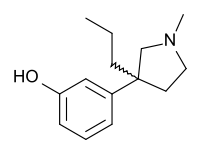

The pharmacodynamic response to an opioid depends upon the receptor to which it binds, its affinity for that receptor, and whether the opioid is an agonist or an antagonist. For example, the supraspinal analgesic properties of the opioid agonist morphine are mediated by activation of the μ1 receptor; respiratory depression and physical dependence by the μ2 receptor; and sedation and spinal analgesia by the κ receptor. Each group of opioid receptors elicits a distinct set of neurological responses, with the receptor subtypes (such as μ1 and μ2 for example) providing even more [measurably] specific responses. Unique to each opioid is its distinct binding affinity to the various classes of opioid receptors (e.g. the μ, κ, and δ opioid receptors are activated at different magnitudes according to the specific receptor binding affinities of the opioid). For example, the opiate alkaloid morphine exhibits high-affinity binding to the μ-opioid receptor, while ketazocine exhibits high affinity to ĸ receptors. It is this combinatorial mechanism that allows for such a wide class of opioids and molecular designs to exist, each with its own unique effect profile. Their individual molecular structure is also responsible for their different duration of action, whereby metabolic breakdown (such as N-dealkylation) is responsible for opioid metabolism.

The first fully synthetic opioid was meperidine (later demerol), found serendipitously by German chemist Otto Eisleb (or Eislib) at IG Farben in 1932.[228] Meperidine was the first opiate to have a structure unrelated to morphine, but with opiate-like properties.[199] Its analgesic effects were discovered by Otto Schaumann in 1939.[228] Gustav Ehrhart and Max Bockmühl, also at IG Farben, built on the work of Eisleb and Schaumann. They developed "Hoechst 10820" (later methadone) around 1937.[230] In 1959 the Belgian physician Paul Janssen developed fentanyl, a synthetic drug with 30 to 50 times the potency of heroin.[211][231] Nearly 150 synthetic opioids are now known.[228]

Tramadol and tapentadol, which act as monoamine uptake inhibitors also act as mild and potent agonists (respectively) of the μ-opioid receptor.[264] Both drugs produce analgesia even when naloxone, an opioid antagonist, is administered.[265]